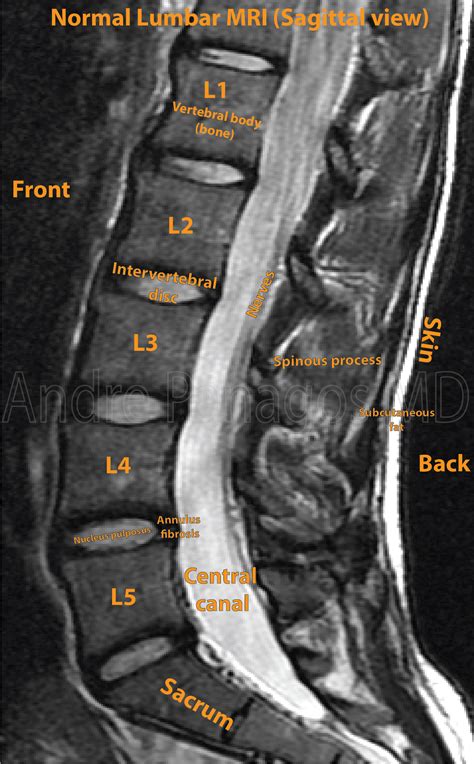

Alright, let’s start with the basics. MRI of the spinal canal , often referred to as a spinal MRI, is a sophisticated medical imaging technique. It’s like taking detailed photographs of the inside of your body, specifically focusing on your spinal cord, the surrounding nerves, and the structures that protect them. Unlike some other imaging methods that use radiation, MRI uses strong magnetic fields and radio waves to create these images. This makes it a safe and painless way to get a clear picture of what’s going on within your spinal canal. The images produced are incredibly detailed, often providing far more information than standard X-rays.

Think of your spinal canal as a vital highway running through your back. It houses the spinal cord, which is like the main cable carrying signals between your brain and the rest of your body. The spinal canal also contains cerebrospinal fluid, blood vessels, and various tissues. An MRI allows doctors to see all these components in exquisite detail, enabling them to diagnose a wide range of conditions. Whether you’re dealing with back pain, numbness, or other neurological symptoms, an MRI of the spinal canal can be a crucial tool in pinpointing the source of the problem. It helps doctors understand the intricate details of your spinal structures without needing to resort to invasive procedures. This diagnostic method provides clear and comprehensive insights, helping your healthcare team to make informed decisions about your treatment and care.